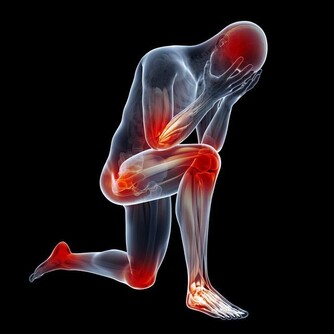

1、全身症狀

疲倦乏力是肝硬化晚期症狀之一,肝硬化晚期症狀多半有皮膚乾枯粗糙,面色灰暗黝黑。